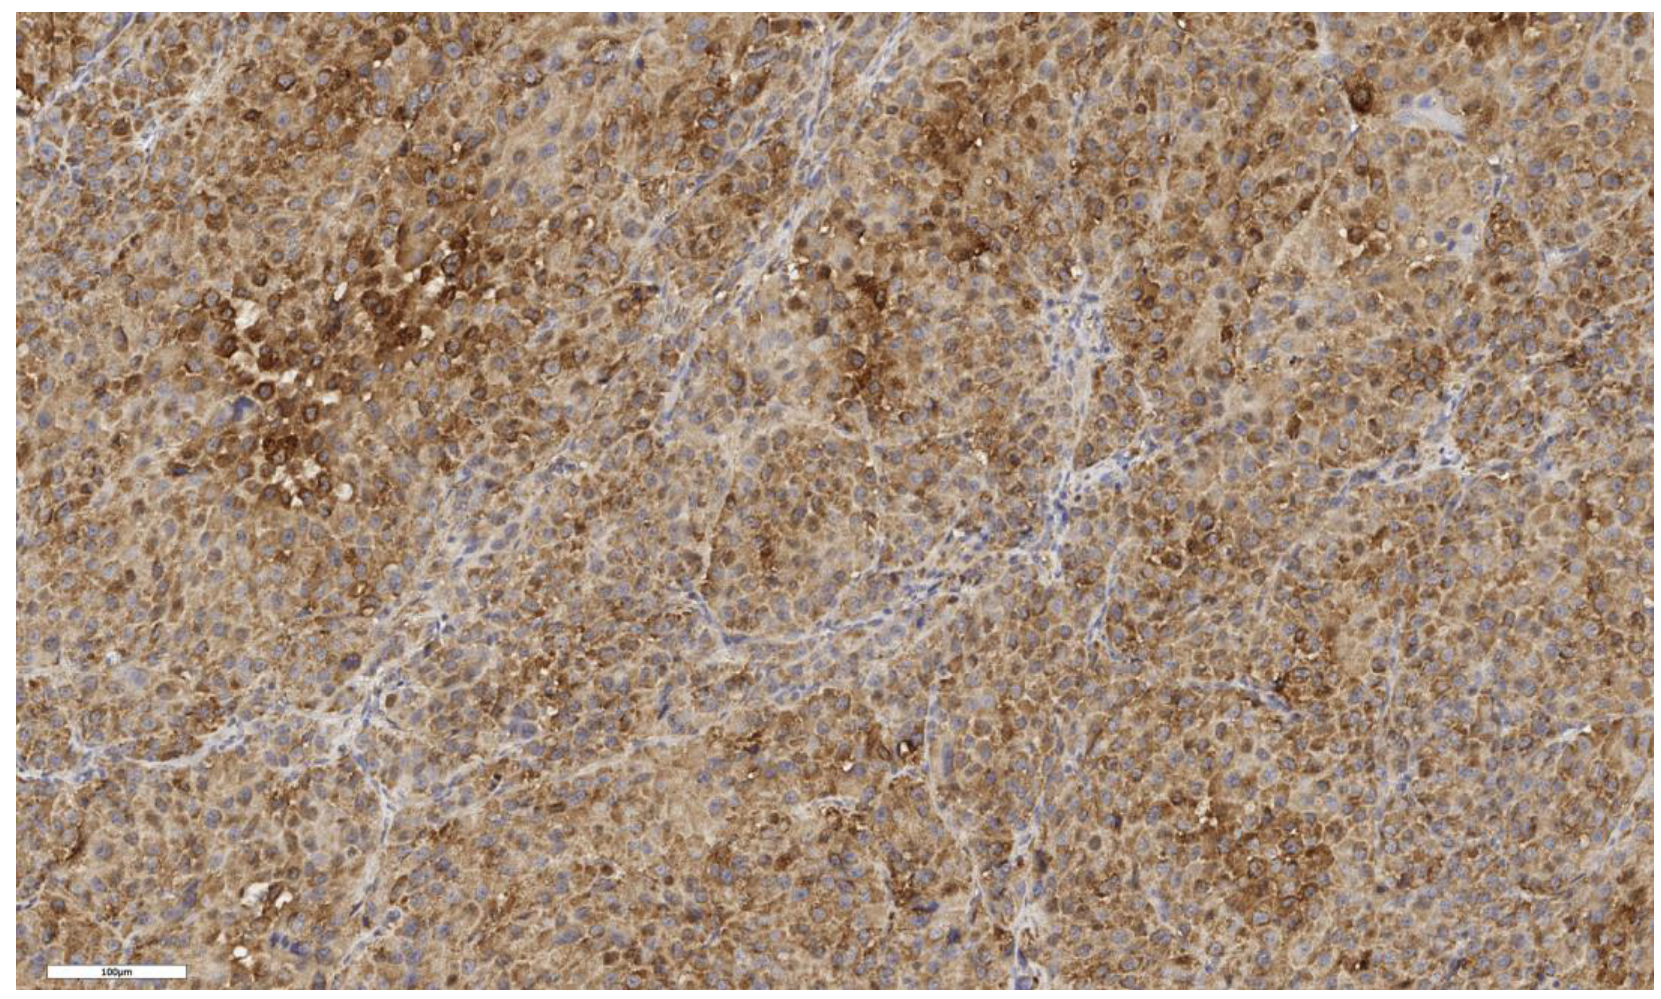

3.2. Analysis of LGR5 Marker Expression